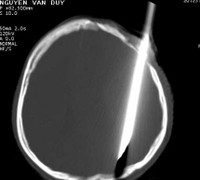

(VTC News) - Trong cuộc hỗn chiến, Duy bị nhóm thanh niên đâm xuyên đầu.